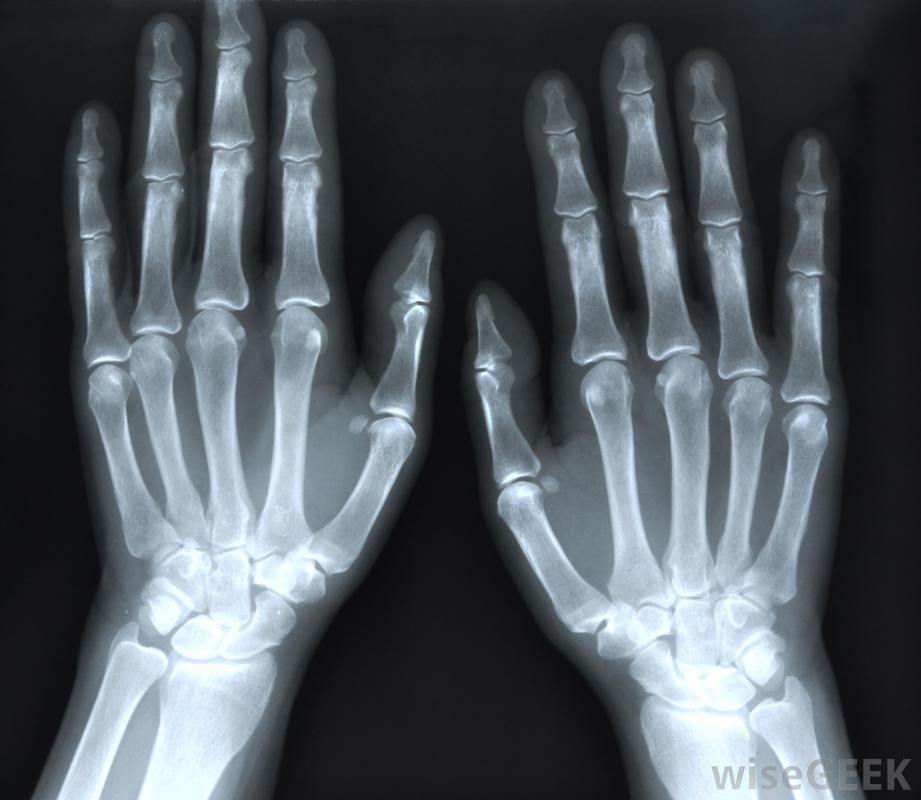

切掉可用于去除人的大脚趾上的骨刺。患有关节炎的人通常会出现骨刺。关节炎会导致关节严重受损,骨刺通常是为了增加受损关节的表面积而形成的。大脚趾关节炎的发展是一种被称为拇趾僵硬的疾病。这是足部关节炎最常见的部位之一关节炎患者常出现骨刺。拇趾僵硬可能会因为对大脚趾功能的限制而出现问题当脚趾从地面上推动时,它向上弯曲的运动有助于使行走成为可能患有拇趾僵硬症的患者,大脚趾可能会变得僵硬,这可能会使行走困难。随着时间的推移,脚趾的有限运动可能会导致脚趾关节卡滞,从而导致额外的不适。在关节过度受损和出现其他并发症之前,接受一次全膝关节切除术可以帮助去除现有的骨刺

大脚趾关节有时会受到骨刺的困扰,导致剧烈疼痛。拇趾僵硬症的症状各不相同。许多有骨刺的人可以看到随着马刺的增长而出现肿块。僵硬和疼痛,可能是尖锐的或持续的疼痛,也可能存在。最常见的发生在大脚趾根部,如跑步等体力消耗可能加重疼痛、发红、形成老茧,大脚趾肿胀也可能是由这种情况引起的在进行全膝关节切除术之前,医生可能会尝试更保守的措施来治疗这种情况。一般来说,改变鞋子的类型将是治疗这个问题的第一步。通常,带有摇杆底的鞋子可以帮助患有拇僵硬症的人。摇杆鞋底通常是弯曲的,并且减轻脚上的压力也可以使用硬底鞋,因为它们不太灵活,行走时会限制大脚趾的运动。